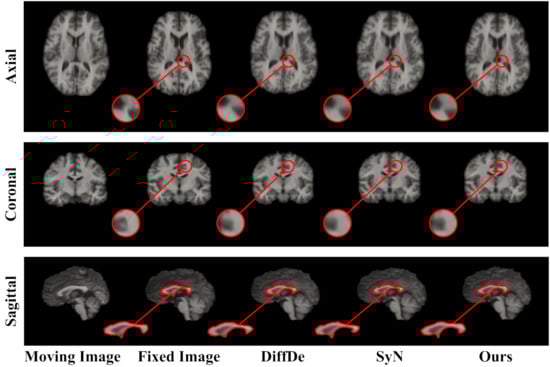

2. Materials and Methods

3. Results

3.1. Implementation Details and Algorithmic Comparison

3.4. The Performance Experiments on the IBSR18 Dataset